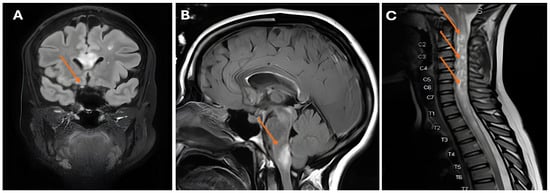

Case 3: Our third case is a woman diagnosed with SLE at 28 years old based on polyarthritis, a malar rash, a positive ANA test (homogenous pattern), and elevated anti-dsDNA antibodies (ELISA; titer 2290 kIU/L; reference: <99 kIU/L), as well as positive anti-Sm antibody tests (anti-SSA, anti-SSB, and anti-Ro52). Her complement C3 levels were lowered (0.65 g/L; reference: 0.9–1.8 g/L), with normal C4 levels. She experienced several thrombotic events, including a pulmonary embolism, cerebral venous sinus thrombosis, and Libman–Sacks endocarditis. These occurred in the setting of secondary antiphospholipid syndrome, confirmed by the consistent presence of lupus anticoagulant (LAC), anti-β2-glycoprotein I (aβ2GP; titer IgG 23 U/mL; reference: 0–7 U/mL), and anti-cardiolipin antibodies (aCL; IgG 65 U/mL; reference: 0–10 U/mL), for which anticoagulative therapy with a vitamin K antagonist was started. She met the 2019 EULAR/ACR classification criteria, with a total score of 21 points [1]. At age 38, she suffered from acute paresis of her right arm and leg, along with nausea and headache, which then progressed to aphasia. Neurological examination identified right-sided hemiparesis and a positive Babinsky sign. A cerebral MRI showed acute disseminated encephalomyelitis (ADEM spectrum). We considered the neurologic manifestations to be compatible with a major flare of her SLE, and we initiated treatment with MPNS pulses (1 g for 3 consecutive days) and cyclophosphamide (once monthly according to the BSA schedule [7]), and our patient recovered with mild cognitive impairment. Her maintenance treatment consisted of low-dose glucocorticosteroids (prednisolone 5 mg once daily) and mycophenolate mofetil (500 mg twice daily). She experienced no flares in subsequent years. However, at age 43, she presented with partial paraplegia and multiple white matter lesions in her spinal cord. Diagnostic evaluation of liquor demonstrated pleocytosis with negative serology and molecular tests for infectious pathogens. We initiated induction treatment with MPNS pulses (1 g for 3 consecutive days) and cyclophosphamide (500 mg every 2 weeks for 6 consecutive cycles according to the Euro-Lupus schedule [8]) under clinical suspicion of a major SLE flare. Following the second dose of cyclophosphamide, the patient developed right-sided optic neuritis with a severe decline in visual acuity (Figure 3). Given that the patient’s neurologic symptoms were both refractory to initial SLE induction treatment and more extensive than is typical for SLE, serological testing for anti-aquaporin-4 (AQP4-IgG) and anti-myelin oligodendrocyte glycoprotein (MOG-IgG) antibodies was performed. The anti-AQ4 antibodies were positive, consistent with the concurrent diagnosis of clinical isolated subtype of neuromyelitis optica spectrum disorder (NOMSD). We switched her treatment from cyclophosphamide to rituximab (2 × 1000 mg), which resulted in clinical improvement. Although NOMSD can be a feature of SLE, in this case, NOMSD presented as a concurrent disease, which rendered a different treatment approach.

Figure 3. (A) Abnormal appearance and pathological enhancement of the right optic nerve (arrow); (B) white matter lesions in the brachium pontis (arrow); (C) longitudinally extensive spinal cord lesion with swelling and the appearance of bright spotty lesions (arrows).

The third patient in our series was diagnosed with SLE and secondary antiphospholipid syndrome, a conclusion substantiated by her compatible clinical phenotype and serologic findings. Her initial neurological manifestation of ADEM, although rare, is compatible with SLE [31] and responded to conventional treatment. Five years later, the patient experienced clinical deterioration that was refractory to induction treatment. Furthermore, the development of a pattern characteristic of a distinct disease entity—specifically, clinically isolated NMO, as evidenced by bilateral optic neuritis (with a severe decline in visual acuity) and multifocal cerebral lesions—compelled us to reconsider an SLE flare diagnosis. Upon positive testing for serum AQP4-IgG, the diagnosis NMO was added to the existing SLE diagnosis. Demyelinating syndromes in SLE patients present with varied phenotypes. It is essential to distinguish between those that represent an SLE flare and those that constitute a concomitant, isolated disease (e.g., clinically isolated NMO [32,33]), as observed in our patient. This differentiation has significant clinical relevance, directly impacting treatment decisions. Our case specifically highlights the importance of not attributing all new manifestations to SLE, demonstrating that they may originate from a concurrent disease, such as isolated NMO.